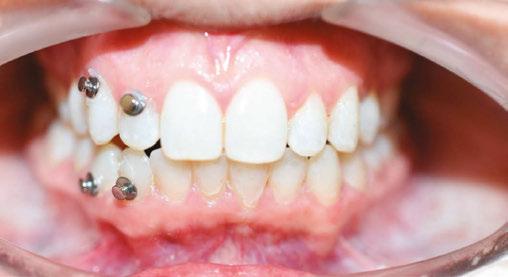

Patient J, a 39-year-old female, (Figures 1, 2, 3, 4, 5, 6) came to the office with concerns about difficulties chewing food and experiencing dry mouth upon waking up in the morning. Additionally, her partner was disturbed by her snoring. Upon examination, several issues came to light:

1. An open bite in the anterior region and a posterior crossbite

2. Breathing through the nose 10% of the time.

3. Lips and cheek muscles actively helping with swallowing food and drinks

4. Lips open 100% of the time

5. Tongue cannot maintain position on a spot, moves between teeth upon swallowing

6. Tongue thrust

7. Weak control over soft palate

Muscle tension around the temporomandibular joint (TMJ) was also evident5 as well as mandibular bilateral lingual torus as response to constant occlusal pressure applied during bruxism.

Figure 2: Anterior view before treatment

Figures 3 and 4: 3. Right side before treatment. 4. Left side before treatment